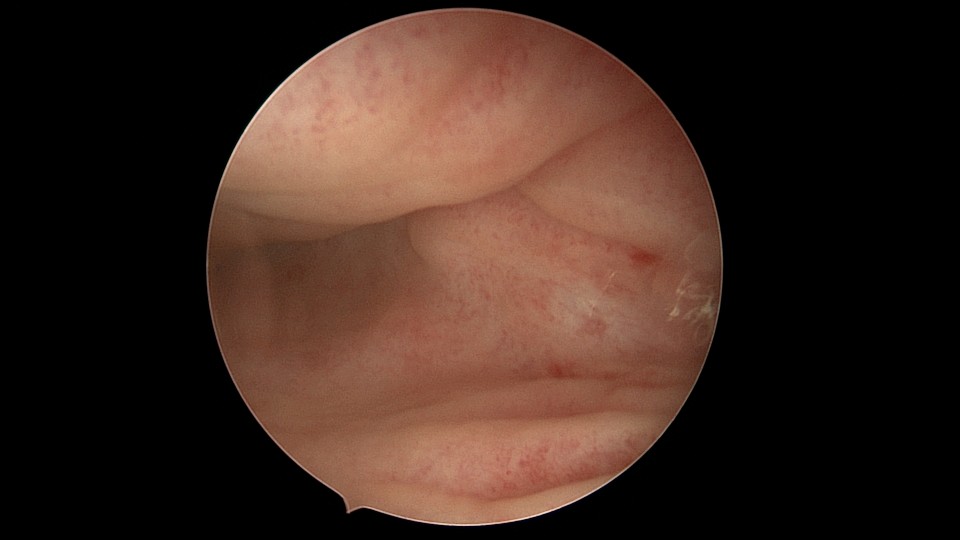

患者54岁,G1P1,剖宫产1次,安环30+年,绝经4年。40年前患者曾行左侧髋关节骨折手术,左下肢外展困难,患者肥胖,阴道很深,金属扩阴器和一次性扩阴器均无法暴露宫颈,用阴道内镜方式进入宫腔,但宫腔镜长度不够,远远能看见环,无法到达环的部位,再次试图暴露宫颈失败,用宫颈钳夹着阴道壁下拉,宫腔镜进入宫腔,但异物钳夹持力度不够,取出失败。用取环钩盲探沿宫腔镜外侧推挤进入宫腔,经历多次拧转,取环钩几乎向前弯成直角,直视下终于钩住节育环,掰直取环钩后缓慢拉出节育环,环变形。